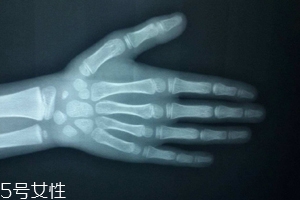

人的生長(zhǎng)發(fā)育可用兩個(gè)“年齡”來(lái)表示,即生活年齡(日歷年齡)和生物學(xué)年齡(骨齡)。通過(guò)測(cè)定骨骼的大小、形態(tài)、結(jié)構(gòu)和相互關(guān)系的變化反映體格發(fā)育程度,并通過(guò)統(tǒng)計(jì)處理,以年齡的形式,以歲為單位進(jìn)行表達(dá)的生物學(xué)年齡。

只需要拍一張左手正位片。

拍攝時(shí),左手五指自然張開(kāi),手心向下,中指與前臂保持中一條直線(盡量不要左右偏,手臂放平不要上抬),X線球管對(duì)準(zhǔn)第三掌骨頭,球管與X光片距離在80CM左右。